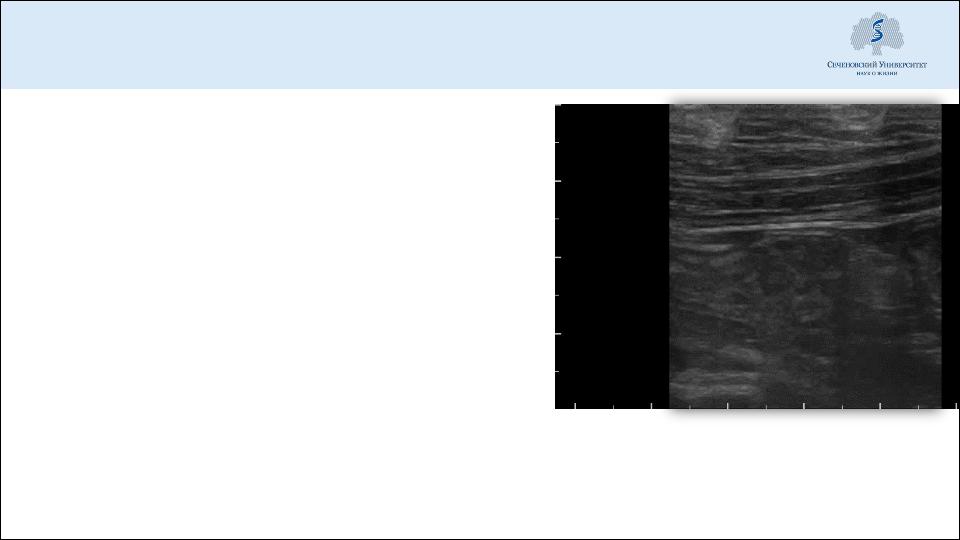

УЗИ – активно перистальтирующие, расширенные петли тонкой кишки

УЗИ (в т.ч. трансвагинальное)